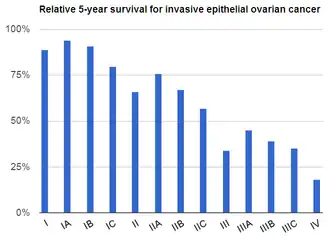

Ovarian cancers are classified according to the microscopic appearance of their structures (histology or histopathology). Histology dictates many aspects of clinical treatment, management, and prognosis. The gross pathology of ovarian cancers is very similar regardless of histologic type: ovarian tumors have solid and cystic masses.[29] According to SEER, the types of ovarian cancers in women age 20 and over are:[66]

| Percent of ovarian cancers in women age 20+ |

Percent of ovarian cancers in women age 20+ by subdivision |

Histology | Five-year RSR |

|---|---|---|---|

| 89.7 | Surface epithelial-stromal tumor (adenocarcinoma) | 54.4 | |

| 26.4 | Papillary serous cystadenocarcinoma | 21.0 | |

| 15.9 | Borderline adenocarcinoma (underestimated - short data collection interval) |

98.2 | |

| 12.6 | Adenocarcinoma, not otherwise specified | 18.3 | |

| 9.8 | Endometrioid tumor | 70.9 | |

| 5.8 | Serous cystadenocarcinoma | 44.2 | |

| 5.5 | Papillary | 21.0 | |

| 4.2 | Mucinous cystadenocarcinoma | 77.7 | |

| 4.0 | Ovarian clear-cell carcinoma | 61.5 | |

| 3.4 | Mucinous adenocarcinoma | 49.1 | |

| 1.3 | Cystadenocarcinoma | 50.7 | |

| 5.5 | Carcinoma | ||

| 4.1 | Carcinoma not otherwise specified | 26.8 | |

| 1.1 | Sex cord-stromal tumor | 87.8 | |

| 0.3 | Other carcinomas, specified | 37.3 | |

| 1.7 | Müllerian tumor | 29.8 | |

| 1.5 | Germ cell tumor | 91.0 | |

| 0.8 | Teratoma | 89.1 | |

| 0.5 | Dysgerminoma | 96.8 | |

| 0.3 | Other, specified | 85.1 | |

| 0.6 | Not otherwise specified | 23.0 | |

| 0.5 | Ovarian squamous cell carcinoma (Epidermoid) | 51.3 | |

| 0.2 | Brenner tumor | 67.9 | |

| 0.2 | Other, specified | 71.7 |